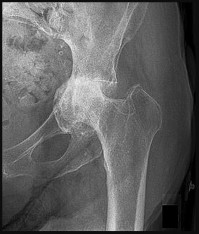

The Ficat and Arlet classification is classically used to stage osteonecrosis of the femoral head based on standard radiographs. Stage I has normal radiographs (but positive MRI). Stage II shows cystic/sclerotic changes without subchondral collapse. Stage III is defined by subchondral collapse, which is classically visualized as the 'crescent sign' (subchondral radiolucency indicating mechanical failure of the trabecular bone), but the joint space remains preserved. Stage IV involves secondary osteoarthritis with joint space narrowing and acetabular changes.